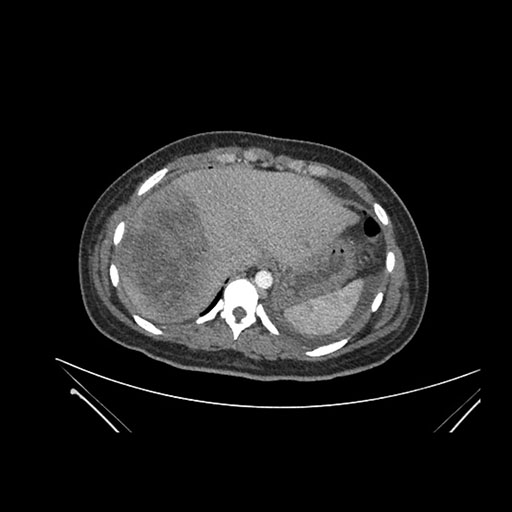

Imaging Analysis

Look through the patient's CT scan to identify any areas of concern for the necessary procedure.

Axial Arterial

Based on initial findings, which issue(s) would you be most concerned about?